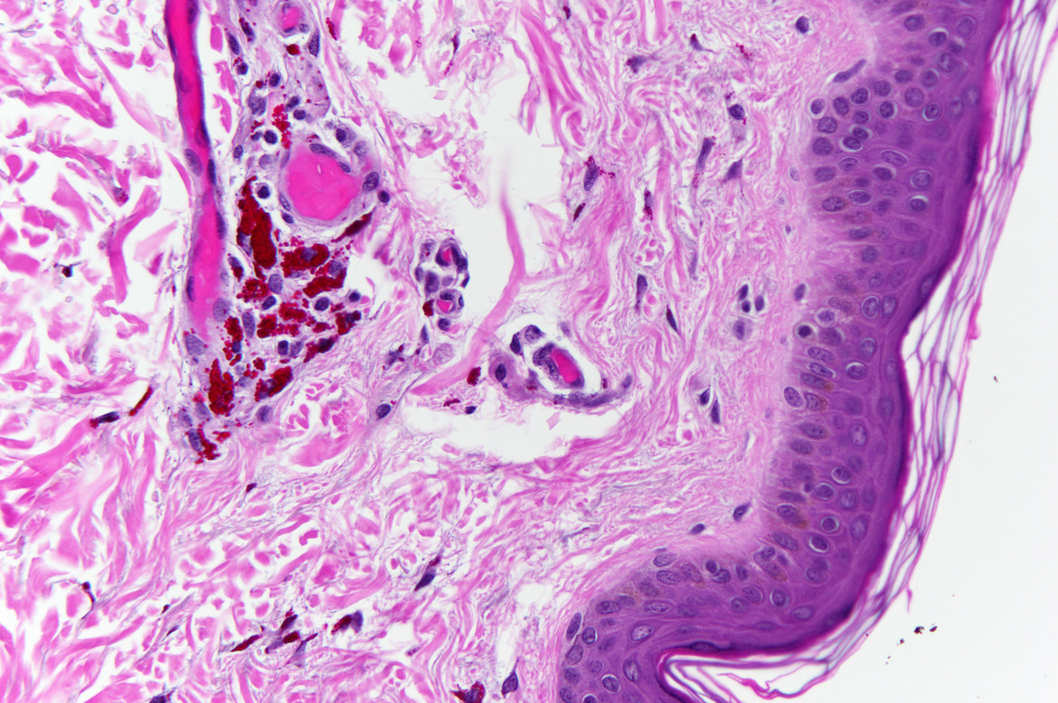

A Tattoo Close Up Posted on 10 Nov 2014 by wyrdwordsandeffigies This is what a tattoo looks up like really, really close up. For a good insight into this surreal image, go here. Share this: Share on X (Opens in new window) X Share on Facebook (Opens in new window) Facebook Share on Pinterest (Opens in new window) Pinterest Share on Tumblr (Opens in new window) Tumblr Like Loading... Related Published by wyrdwordsandeffigies My name is Katie Metcalfe and I’m an English author, blogger, poet and songwriter. I have a northern fever and tend to be a bit too wyrd for most people. View all posts by wyrdwordsandeffigies